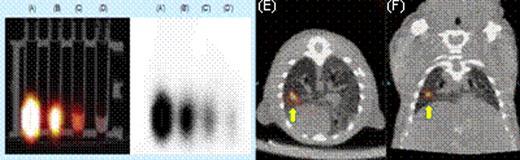

SPECT Imaging. (A) through (D) show the radioactivity of electro-transferred 111In-GNPs into T cells. (E) axial and (F) coronal views of directly injection of T cells containing111In-GNPs.